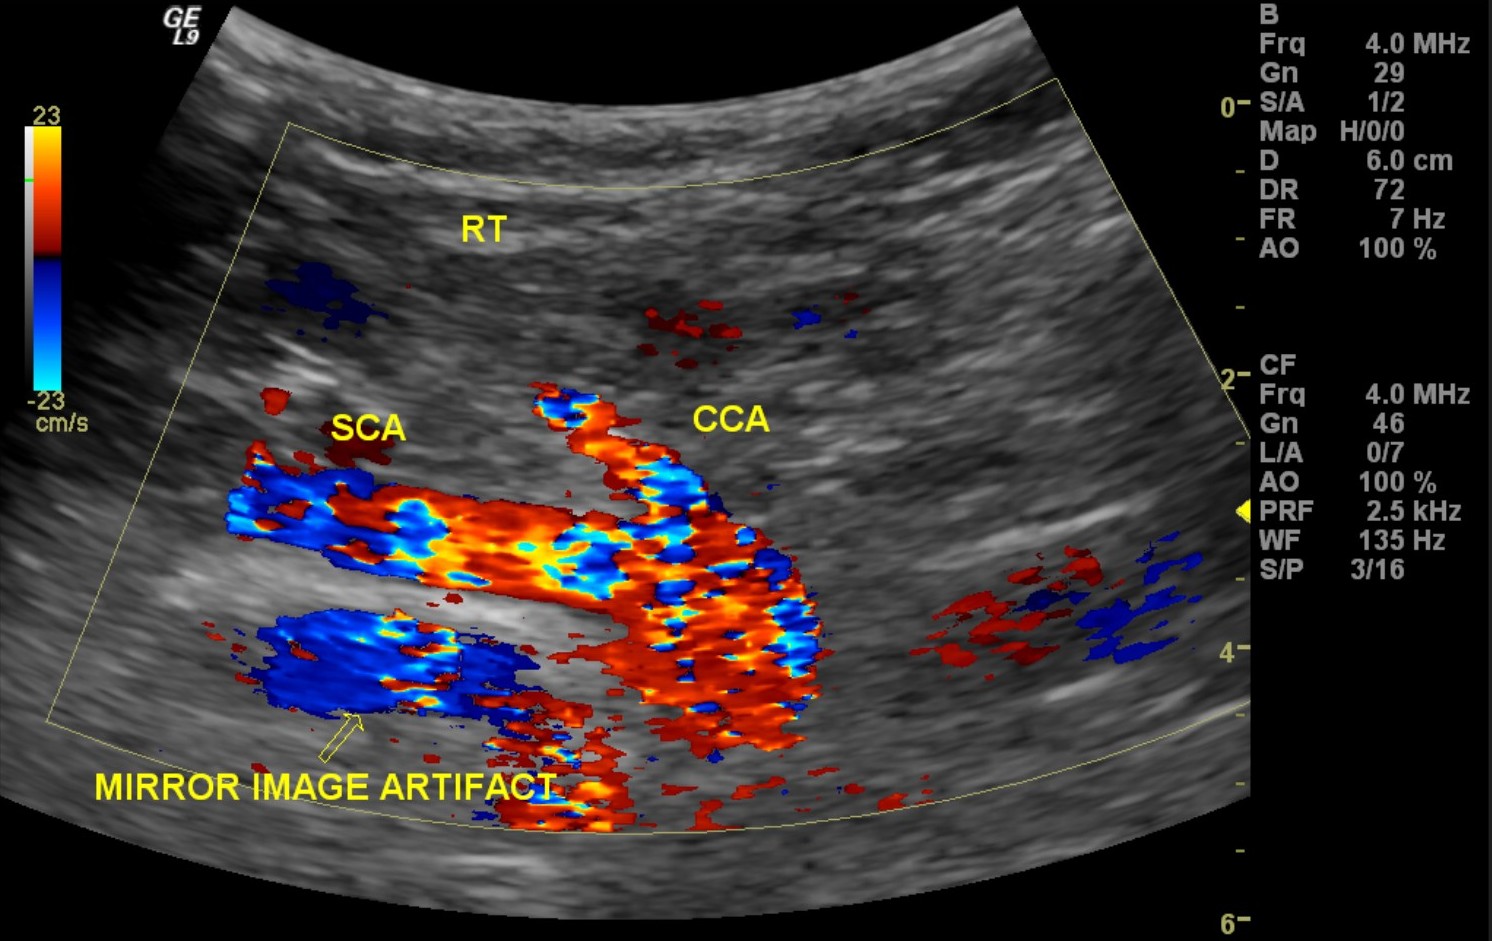

From www.nysora.com

Ultrasound image artifacts explained NYSORA NYSORA What Does Artifact Mean On Ultrasound an artifact is something that you see on the ultrasound image which is either not really there, is in another place in reality, or looks different than it. ultrasound artifacts are commonly encountered and familiarity is necessary to avoid false diagnoses. ultrasound artifacts represent a false portrayal of image anatomy or image degradations related to false assumptions.. What Does Artifact Mean On Ultrasound.